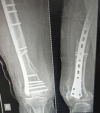

Introduction: Distal femur fractures are mostly caused due to vehicular injuries in the middle-aged population. Operative treatment has been preferred with open reduction and internal fixation in these fractures. Due to the availability of anatomical locking compression plates (LCPs), better results and improved functional outcomes have been observed. This study aims to observe the surgical outcome of distal femur fractures operated with an anatomical LCP.

Materials and methods: A prospective study was carried upon 48 patients with 40 male and 8 female patients having fractures of the distal femur. The mean age of presentation was 40.6 years. Thirty of them had vehicular injuries and 18 had a history of fall. Open fractures were seen in 22 patients and associated ipsilateral limb injuries were seen in 16 and contralateral limb injuries were seen in 8 patients. The patients were treated with anatomical LCP. The lateral approach was used in all cases for my study.

Results: The mean follow-up in the present study was 6 months. All fractures were united with a mean union period of 18.2 weeks. At final follow-up, fixed flexion deformity was seen in 25% of the patients. There were 16 cases of infection with 2 being a superficial infection treated conservatively and 14 cases having a deep infection treated with debridement and antibiotics. 2 cases of nonunion, 4 cases of malunion and 4 cases of delayed union were observed. 16 cases develop joint stiffness. 16 cases also developed limb shortening and 10 had fixed flexion deformity and 8 had varus deformity. At the time of final follow-up through "SCHATZKER AND LAMBERT SCORING SYSTEM," satisfactory outcomes were achieved in 50% (20.8%excellent and 29.2% good) of the patients.

Conclusion: Distal femur fracture treated with anatomical LCP needs careful anatomical reduction, rigid fixation and early knee mobilisation and weight bearing on signs of healing with an early presentation to the hospital from the time of injury were the essential factors in achieving better outcome for the patient.